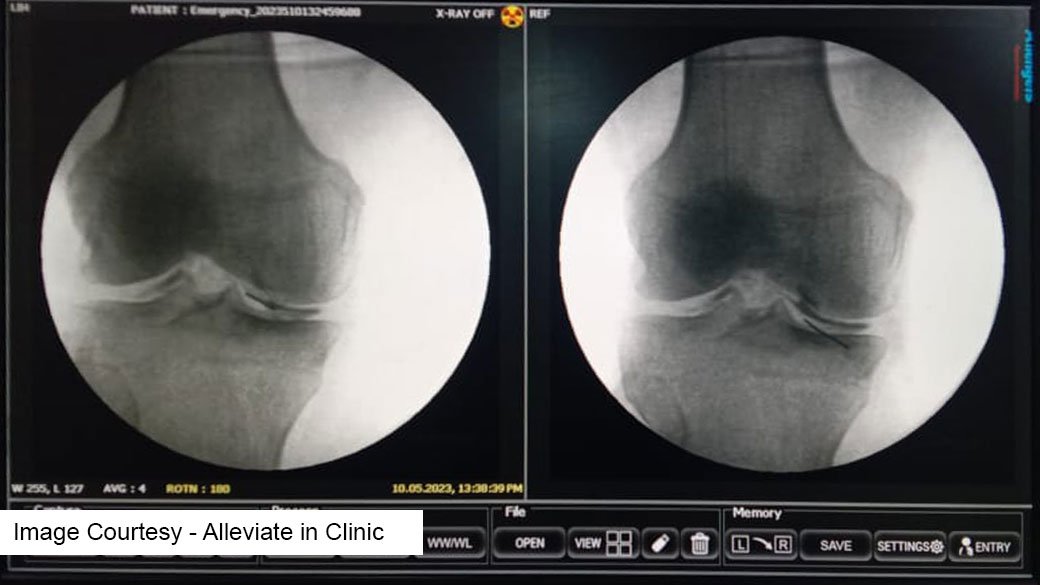

• Image-Guided Treatments: Utilizing advanced imaging techniques to accurately diagnose knee conditions and precisely administer PRP and Prolotherapy injections.